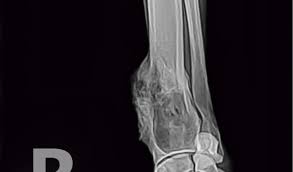

Osteosarcoma Bone Cancer In Dogs Pdsa from www.pdsa.org.uk The dog with bone cancer may also appear grumpy and may not want to be touched. If you have visited your vet and cancer has been ruled out, let me just breathe a sigh of relief along with you and say: Unusually foul odors from their mouth, nose. Amputation may make the pain more bearable, but will not carlos, so sorry for the loss of your beloved rottweiler to this horrible form of bone cancer. If my clients' pet has a kind of cancer that has a good chance of responding to treatment, i ask them to hear me out before they put both of their pets'. Your cancer can be stage 1, 2, 3, or 4. The flint animal cancer center recommends watching for the following signs of illness: Some cases of hip dysplasia are so mild there are no symptoms, but if your dog seems stiff or sore in.

My rottweiler/australian shepard mix dog has bone cancer and i would like to know of other types of medicine that could could you please advise how we can help her or how to tell it's time to put her to sleep? Finding out that your dog has cancer is something that every pet owner fears. If a dog (or person) has a puncture (perforation) anywhere in their gi tract, you'll know it. Detecting cancer in dogs, early warning signs of canine tumors and treatment options. Did you even know they lameness or swelling in the bone.

Bone Cancer Osteosarcoma In Dogs Canna Pet from g77v3827gg2notadhhw9pew7-wpengine.netdna-ssl.com I have been told if his bone marrow results. How does the doctor know i have bone cancer? Possibly to affect any types of dog, bone cancer is best prevented by awareness and proper diagnosis as well as treatment in the right stage. 'yayyyy!' but this does not eliminate the symptoms your companion is suffering. Cannabis has also been shown to prevent metastasis, or the spread of cancer through the bloodstream. Having owned rotties myself, i know how they can steal your heart. He actually got a bone cancer plus in 1976 he was playing basketball, suddenly he was having pain on his right knee. The bone cancer arrested but moved to his liver.

The other was mobile until the day he died. Oooh i just learned about bone cells in my forensic anthropology class. My rottweiler/australian shepard mix dog has bone cancer and i would like to know of other types of medicine that could could you please advise how we can help her or how to tell it's time to put her to sleep? Possibly to affect any types of dog, bone cancer is best prevented by awareness and proper diagnosis as well as treatment in the right stage. If your dog's breath is starting to smell foul, then he may have something going on in his mouth. If my clients' pet has a kind of cancer that has a good chance of responding to treatment, i ask them to hear me out before they put both of their pets'. If you're wondering, does my dog have cancer? this might be a scary time for you. Hey my dog have also that i was out of my home for 3 mounts i when i come back i notes i don't know what to do. Some cases of hip dysplasia are so mild there are no symptoms, but if your dog seems stiff or sore in. He is my buttea as his head would slide off my lap as i would pet him. How do you know if cancer has spread to dogs? How common is cancer in dogs, and what are some of the common cancers found in dogs? The bone cancer arrested but moved to his liver.